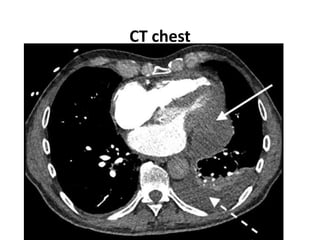

• CT chest with contrast to characterize

CT chest

CT chest findings

• Loculated pericardial effusion with mass effect

• High attenuation adjacent to LAD, extending

into pericardial fluid

• Left sided pleural effusion, in continuous with

pericardial effusion

• Left lung base atelectasis

• Extensive ground glass opacities